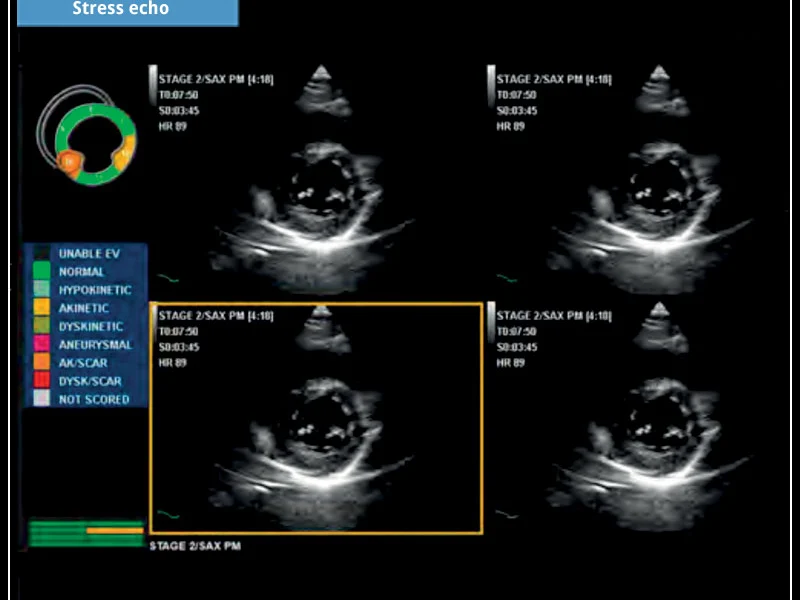

MyLab™X5 is equipped with comprehensive cardiac and vascular configurations. It functions as a complete system for ultrasound cardiovascular examination, and features customizable measurements and reporting.

General Imaging Cardiovascular